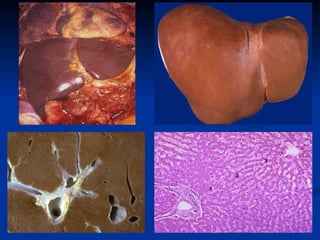

Pathology  Type of hepatic cirrhosis: M acronodular cirrhosis ,  ф >3.0 mm M icronodular cirrhosis ,  ф <3.0 mm Mix: Macro- +Micro-nodular cirrhosis

Ongoing liver damage with liver cell necrosis followed by fibrosis and hepatocyte regeneration results in cirrhosis. This produces a nodular, firm liver. The nodules seen here are larger than 3 mm and, hence, this is an example of macronodular cirrhosis.  This is an example of a micronodular cirrhosis. The regenerative nodules are quite small, averaging less than 3 mm in size. The most common cause for this is chronic alcoholism. The process of cirrhosis develops over many years.  M acronodular cirrhosis M icronodular cirrhosis >3.0mm <3.0mm Mix is including maro- and micronodular cirrhosis  Pathology